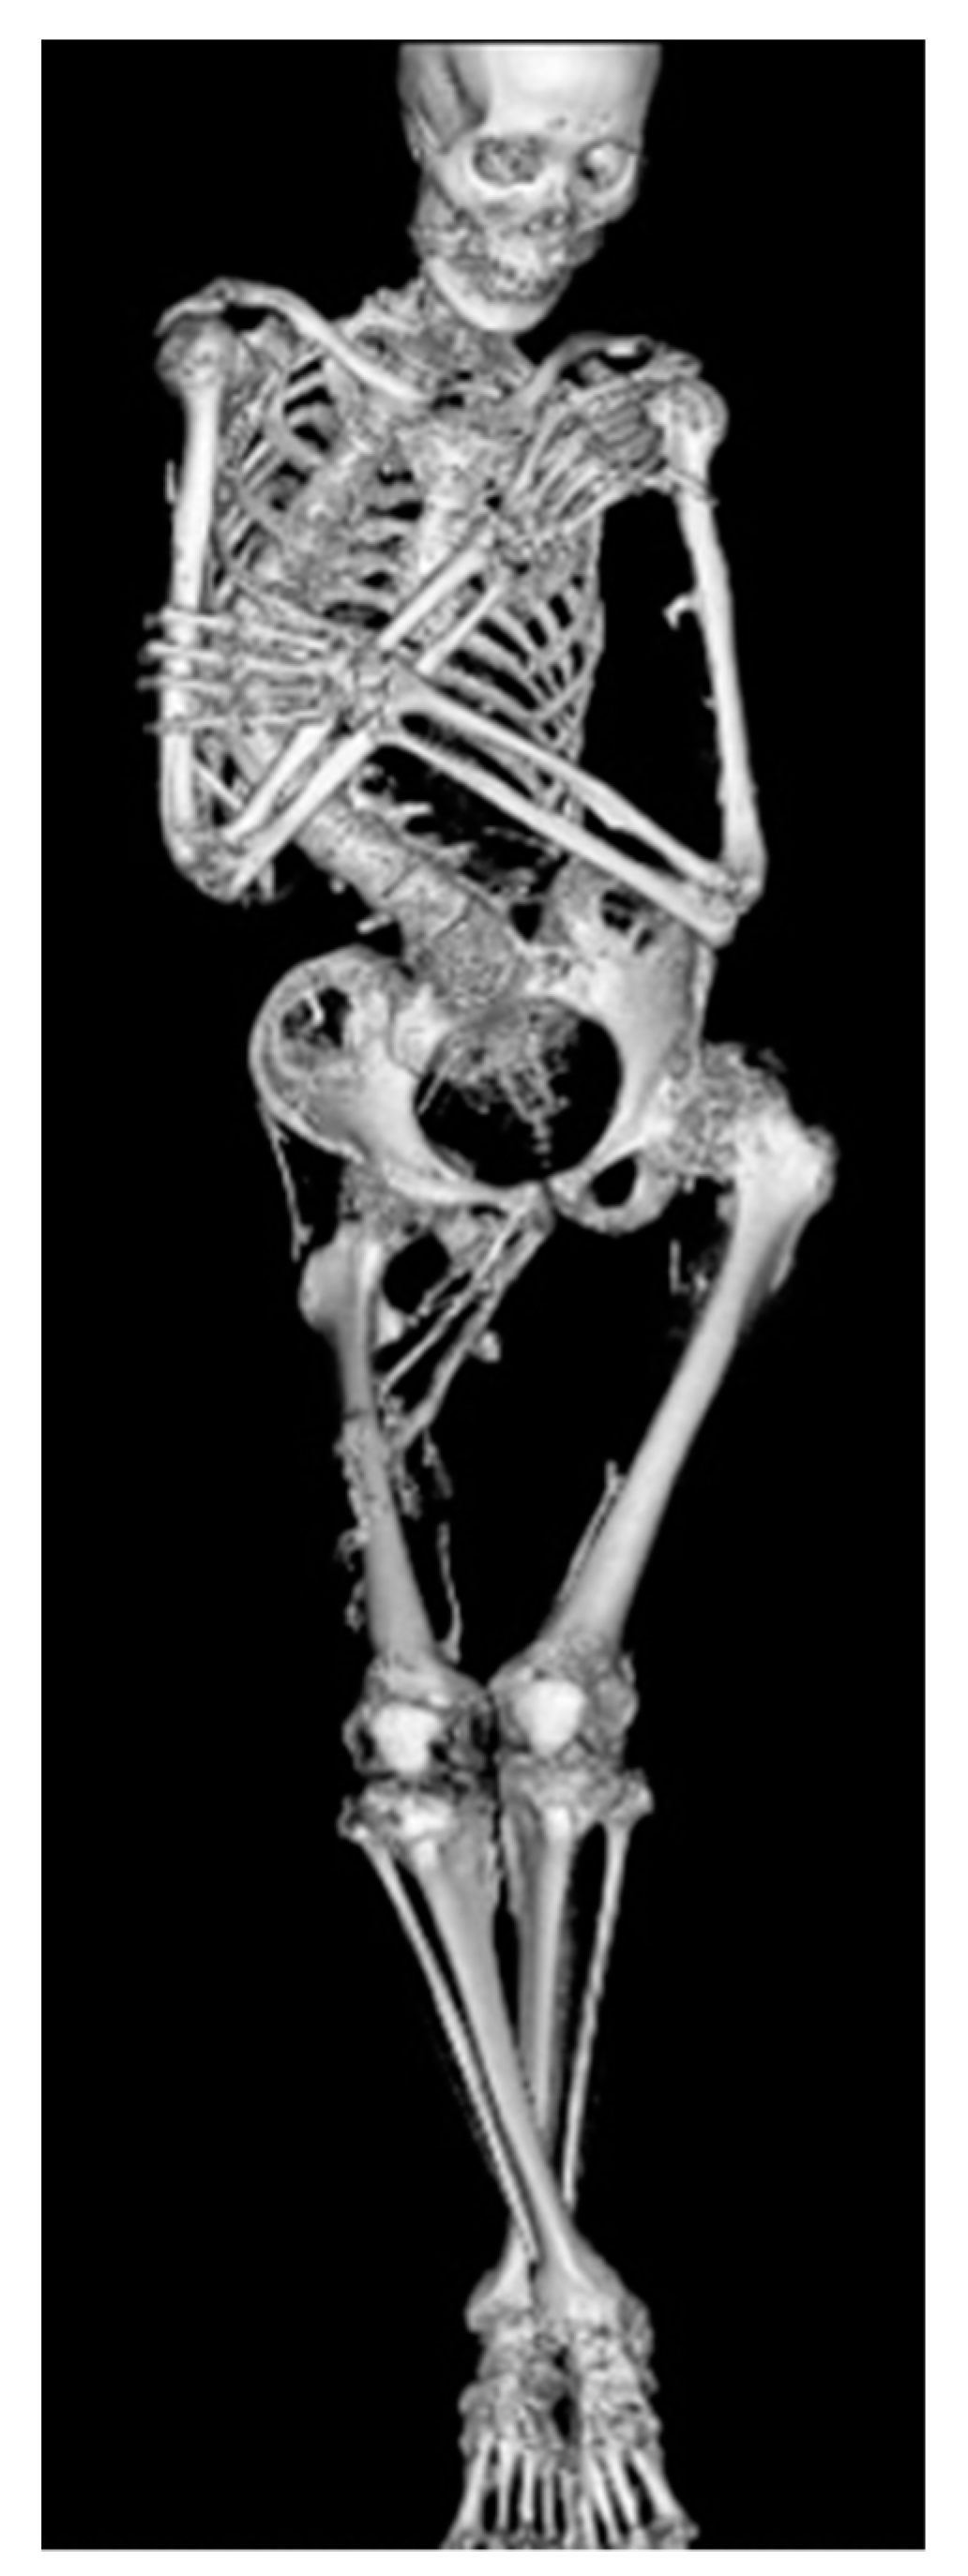

4. Natural Clinical Course

5. Skeletal Malformations